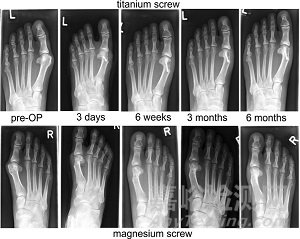

近幾年先后有純鎂及鎂合金材料的臨床植入研究報道。2013年,Windhagen等進行了MgYREZr合金空心螺釘進行腳拇指外翻手術后固定的臨床研究工作。MgYREZr合金螺釘植入的6個月內,在植入部位沒有觀察到排異反應、骨溶解以及炎癥反應,同時也未見跖趾關節(jié)強直現(xiàn)象。影像學檢測表明,植入物部位沒有發(fā)生缺血性壞死以及氣體聚集。植入6個月后,MgYREZr合金螺釘未全部降解,骨組織已經(jīng)完全愈合(圖4)。

可

圖4 輕度拇外翻畸形的術x光片(鎂螺釘與鈦螺釘?shù)闹踩雽Ρ龋?/span>